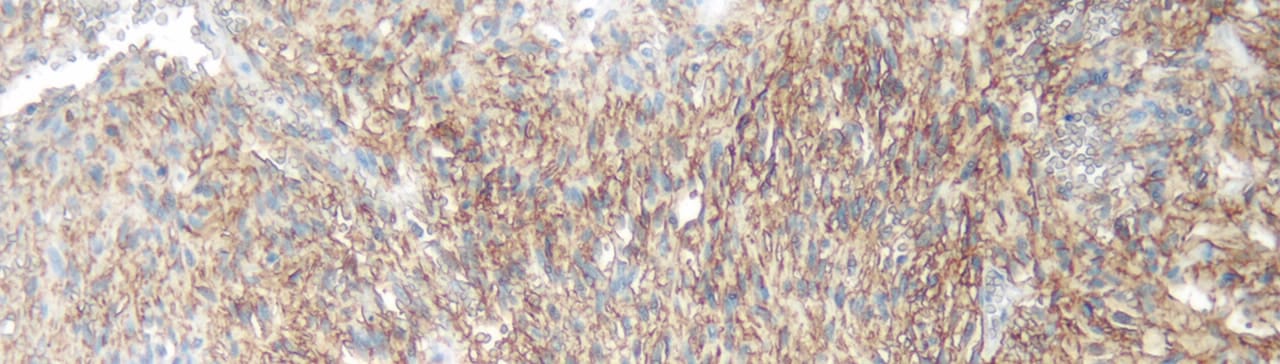

c-kit, otherwise known as CD117 and stem cell factor receptor, is a 145 kDa type III transmembrane receptor tyrosine kinase encoded by the c-Kit proto-oncogene. Studies suggest that the c-Kit gene product is closely related to the process of malignant transformation, and to the pathogenesis of some specific types of human solid tumors.